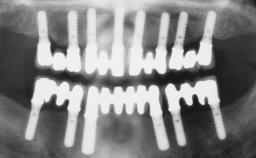

Immediate Loading of Six Implants in the Maxilla and Final Restoration with a Full-Arch Gold/Ceramic FDP Involving the Concept of Tilted Implants

# of Implants 6

Type of Implants One-Piece|Reduced-Diameter

Bone Augmentation Horizontal|Simultaneous

Surgical SAC classification

SAC Level Complex

Defining Characteristics Fully edentulous upper jaw to be rehabilitated with four or more implants

Modality Fixed hybrid bridge on 5+ implants